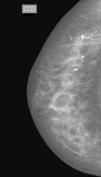

Calcificaciones amorfas:

También llamadas «en polvo», «nube» o «algodonosas», corresponden a calcificaciones tan pequeñas (menores a 0,1mm) que no es posible contarlas ni determinar su forma. De ahí su nombre «a-morfas» (sin forma) (fig. 18). Para catalogarlas como amorfas estas calcificaciones no deben decantar en las proyecciones laterales estrictas, pues en este caso corresponderían a calcificaciones en «lechada de cal». Muchas de ellas son benignas, como las originadas en cambios fibroquísticos, especialmente cuando son difusas y bilaterales23. Sin embargo, cuando están agrupadas, presentan una distribución segmentaria o lineal12. Pueden deberse a lesiones de alto riesgo o etiología maligna, lo cual justifica su indicación de estudio histológico. El valor predictivo positivo es de aproximadamente un 20%, por lo que se incluyen en la categoría 4B12.